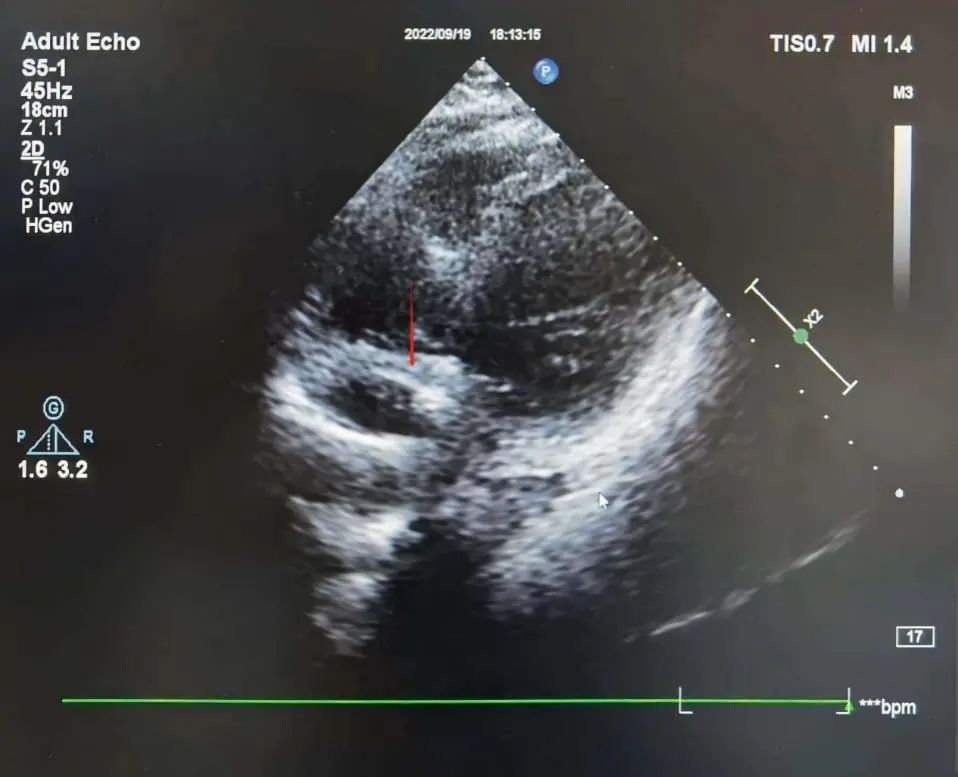

彩超下观察心房导线位置,呈“U”型挂于心耳

心房电极放置:心房电极经上腔静脉进入右心房,在超声下观察电极进入右心耳位置,在起搏条件下进行微调,观察实时心电图,在1.0V可起搏情况下,观察超声电极状态为“U型”,张力良好。

心房电极测试参数为:阈值:0.7V,P波:3.0mv,阻抗:710Ω。